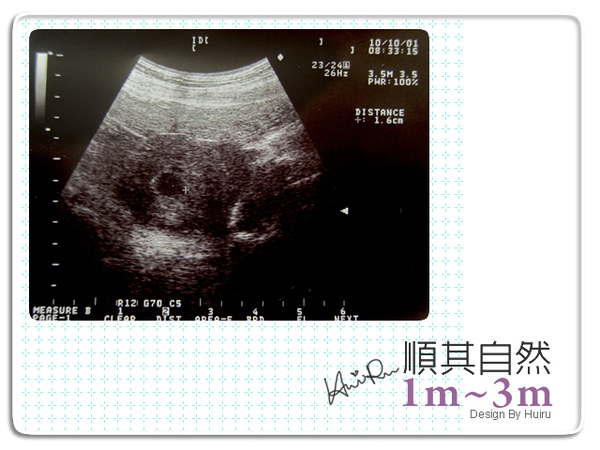

10月01日

自從有這個小子之後,經常不定期的出血,孕吐的狀況也比第一胎嚴重,今早請了假來給醫師看一下,醫師幫我打了安胎針,也開了點藥給我吃,哇賽!安胎真還真不是普通的痛,姐告訴我那是油劑會痛一個月,我的媽呀><~

今天醫師給我一張超音波,恩還只是個胚胎,喔喔一個圈1.6cm~啥都看不到